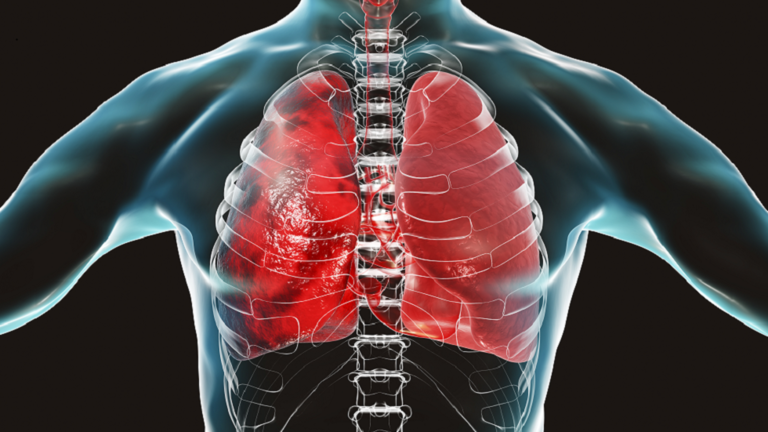

والعمليات المدمرة تبدأ خلال ذروة العدوى في الأسابيع التي تلي هزيمة الفيروس، ما يؤدي إلى تلف الأعضاء ويسبب مرضا مزمنا أو حتى الموت. وبعد نوبة أولية من "كوفيد-19"، على سبيل المثال، يعاني البعض من السعال المستمر وصعوبة وضيق التنفس، وهي علامات تدل على استمرار مرض الرئة.

وعند دراسة الفئران، وجدوا أن العدوى تؤدي إلى ظهور بروتين يسمى IL-33، وهو أمر ضروري للخلايا الجذعية في الرئة لتنتشر في المساحات الهوائية، وتزيد من إنتاج المخاط والالتهاب في الرئة.

وتستحوذ الخلايا القاعدية على المسالك الهوائية الصغيرة والحويصلات الهوائية بينما تظل خلايا AT2 محصورة في الأكياس الهوائية. وتصبح بعض الخلايا القاعدية الجديدة خلايا منتجة للمخاط بينما يطلق البعض الآخر جزيئات تجند الخلايا المناعية إلى الرئتين. وإجمالا، تؤدي العملية إلى انخفاض مساحة الهواء في الرئتين، وزيادة المخاط والالتهاب المستمر، ما يؤدي معا إلى إعاقة التنفس.